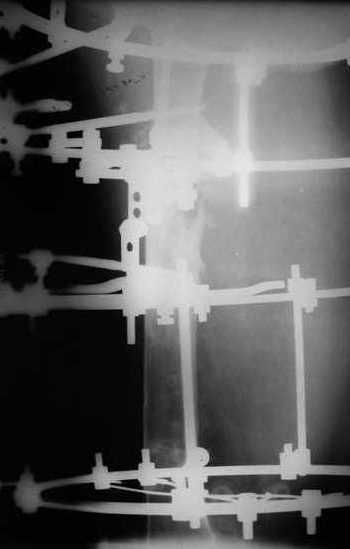

Вчера сделали рентгенограммы бедра нашему пациенту. Угловое смещение нам удалось исправить.

Сейчас проводим дистракцию (2 см).